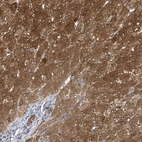

Immunohistochemical staining of human liver shows distinct cytoplasmic positivity in hepatocytes and bile duct cells.